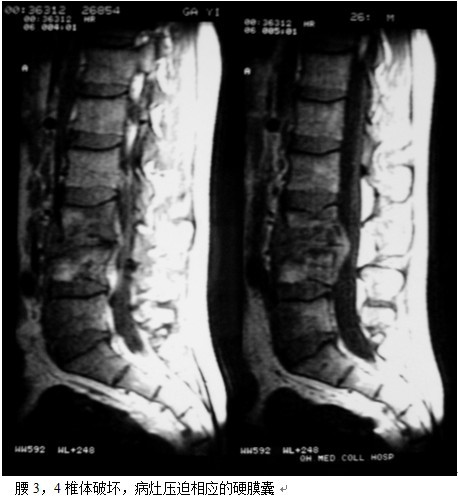

本组46例中男28 例,女18 例。年龄17~67岁,病程6 个月~7年,平均11.3 个月。本组患者均为 L1~S1腰段结核。病灶累及2 个椎体31例(L1-2 6例, L2-3 8例,L3-4 10例,L4-5 5例,L5-S1 2例),3 个或3 个以上椎体15例。合并腰大肌脓肿23列,所有患者均有腰背部疼痛,活动受限,双下肢感觉麻木19例,会阴部感觉减退12例,双下肢肌力减弱12例,腱反射减弱12例,术前后凸角(Cobb 角) <30°者12例, 30°~60°者28 例, >60°者6 例,Cobb角平均32.3°4例患者是二次手术。术前均行X线片、CT或者MRI检查。术后病理检查确诊为脊柱结核。